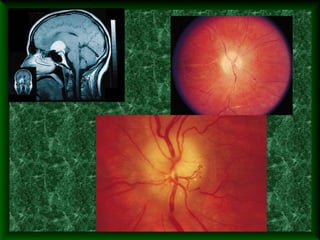

Синдром Форстнера- Кеннеди.Картина

атрофии з.н. На правом глазу и застойного

соска на левом.На рентгенограмме

локализация опухоли справа.

Fully developed papilledema. Advanced

papilledema in a patient with pseudotumor

cerebri. There is marked disc elevation and

vessel engorgement bilaterally with

complete loss of the disc margins and

central cup.